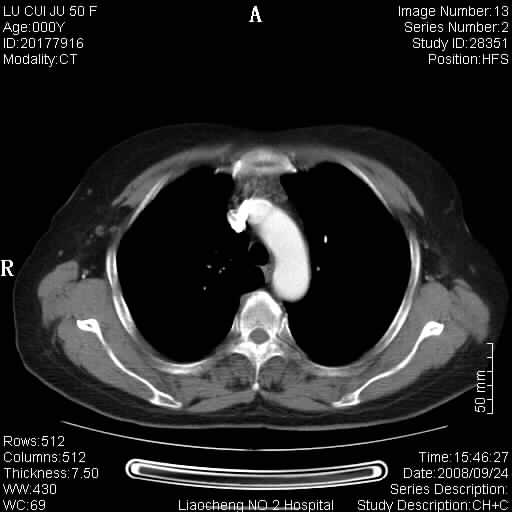

标题: CT15870:F50Y,纵膈占位,是不是胸腺瘤,请各位高手讨论。

临床表现为重症肌无力;ct增强扫描可见前纵膈胸腺部位弥漫性簇状软组织节结灶,不知道是不是胸腺瘤,请各位高手讨论。

考虑胸腺增生

考虑胸腺增生!!

胸腺组织残留